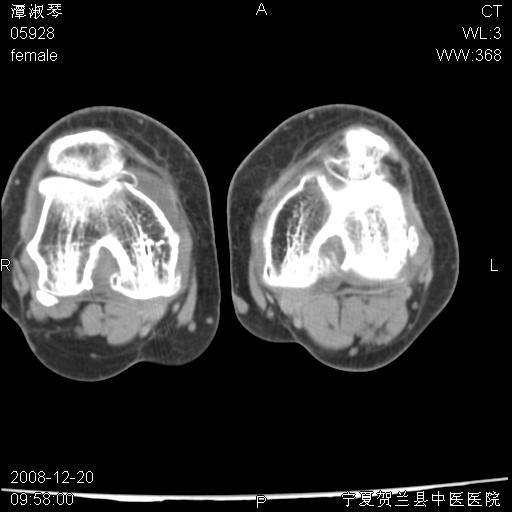

标题: CT17526:请各位看看是啥? [打印本页]

标题: CT17526:请各位看看是啥?

支持骨梗死,退行性骨关节病,膝关节积液.

考虑骨梗死可能性大

骨梗死可能性大

左股骨下段骨梗死。双膝退变。

左胫骨下端松质骨及髓腔内可见点片状高密度灶,骨皮质无明显膨胀及变薄。病变范围较长。支持骨梗死,退行性骨关节病,膝关节积液